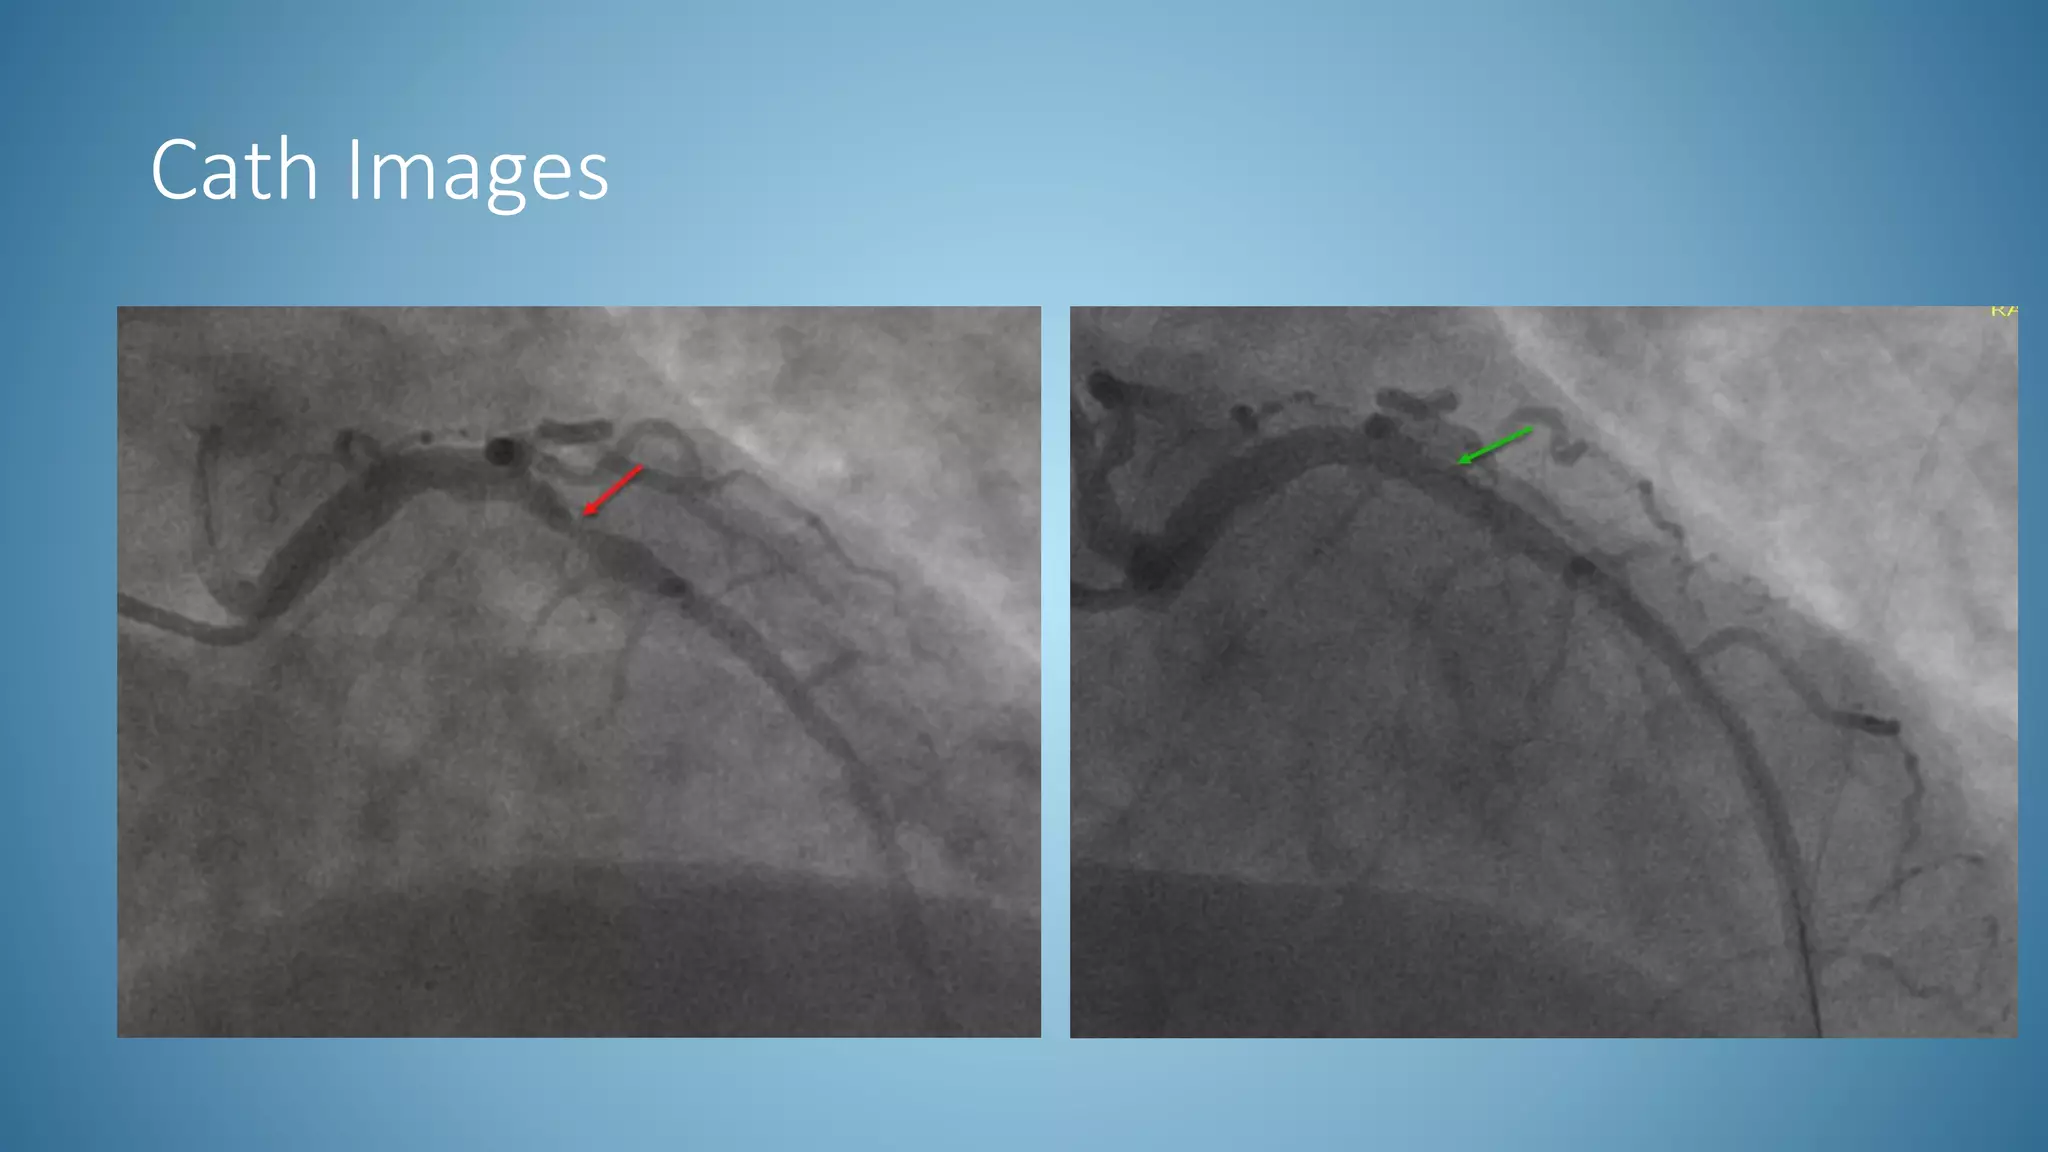

Cath Images

• STEMI activated off of second EKG

• Trop elevated at 2.78

• Emergently taken to cath lab: pt in acute cardiogenic pulmonary

edema in the setting of recent, though more than 48 hours, acute

anterior MI; successful treatment of a proximal hazy 80% thrombotic

LAD lesion w/ stent

• Repeat echo was done 2 days after STEMI and showed an improved EF

of 35-40%

• 4 day admission stay, discharged home